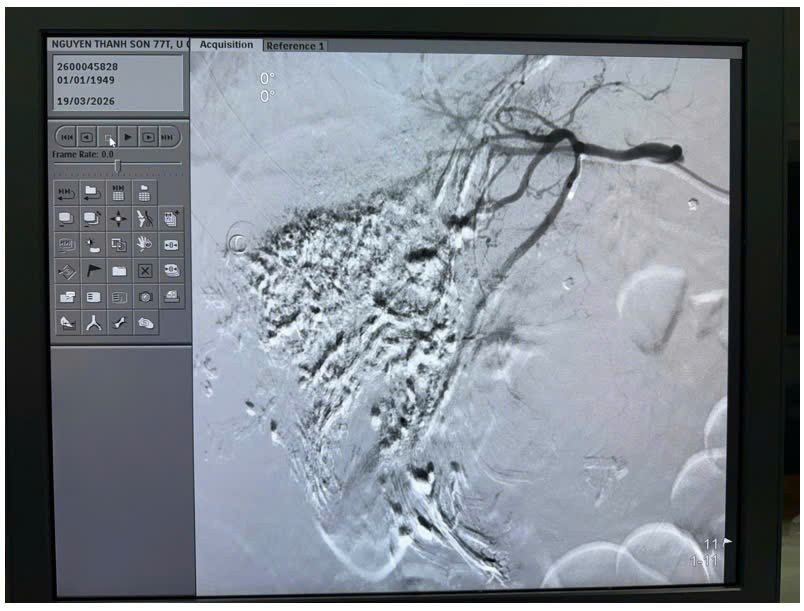

Sau hội chẩn liên chuyên khoa, ê-kíp

quyết định lựa chọn phương pháp can thiệp nội mạch – nút mạch hóa chất (TACE)

nhằm cầm máu và kiểm soát khối u. Dưới hướng dẫn của hệ thống chụp mạch số hóa

xóa nền (DSA), các bác sĩ tiến hành chọn lọc động mạch nuôi khối u và thực hiện

nút mạch bằng vật liệu chuyên dụng kết hợp hóa chất. Kết quả can thiệp đạt hiệu

quả cao, làm tắc khoảng 90% hệ thống mạch máu nuôi khối u, kiểm soát tốt tình

trạng chảy máu.